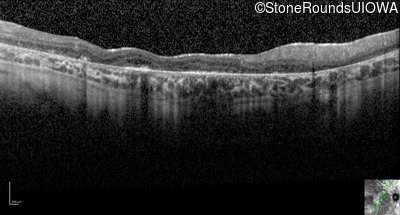

Optical Coherence Tomography - Right - 20/200 +2

Exemplar / OCT Stack